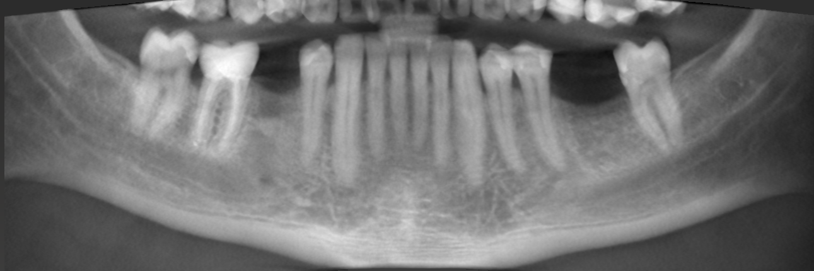

Prosthetically driven backward planning, wherein the desired restorations guide the surgical phase, has modified the approach to contemporary implant dentistry. In addition, due to technological advancements, powerful equipment for the best virtual implant planning and accurate implant installation is available. Resources, which include intraoral scanners (IOS) and cone-beam computed tomography (CBCT) devices, allow the creation of digital 3-dimensional (3D) affected person models using virtual datasets in Standard Tessellation Language (STL) and Digital Imaging and Communications in Medicine (DICOM) codecs. These datasets are aligned with the prosthetic setup, which uses dedicated implant-making plans software in a method named registration.

Current studies suggest that static computer-assisted implant surgical procedure (sCAIS) is more predictable and correct than freehand implant placement because the surgical template guides the drilling and implant setup series to the in-reality planned function (Schneider et al. 2021). Accuracy is paramount to avoid unfavorable essential anatomical systems, along with adjacent roots, nerves, vessels, and sinuses, and to enhance implant number one balance.

Moreover, digital implant-making plans may additionally reduce or even remove the need for hard-tissue augmentation approaches in selected cases by choosing shorter or inclined implants.